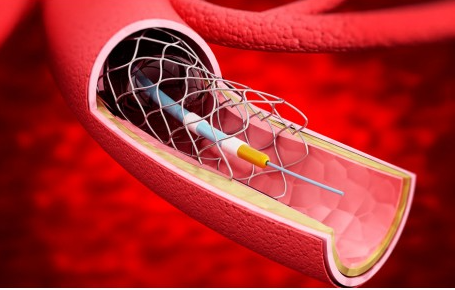

Stents

Gureater ™ CoCr Stent with Sirolimus Coating

GuReater™ is a Cobalt-Chrome drug-eluting stent coated with Sirolimus.

Its 75 μm CoCr struts provide excellent flexibility and crossability, ensuring optimal vessel conformity after implantation.

Available in a wide range of sizes, the Gureater drug-eluting stent features a cobalt-chrome (CoCr) platform with a bioabsorbable polymer (PLGA) that promotes early endothelialisation, helping to prevent inflammation.

Combined with Sirolimus, it offers excellent drug-release control over a total period of 90 days. Its design ensures high flexibility, optimal crossability, and low recoil.

The Co-Cr stent offers high radiopacity and biocompatibility, providing an excellent balance between radial strength and flexibility.

PLGA Biodegradable Polymer of Drug Coating

Drug completely release in 90 days

PLGA coating completely degraded in 180 days

75 µm CoCr Strut

Provide super flexibility and crossability

Ensure the great compliance after implantation